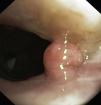

Figure 2. Rigid bronchoscopy performed to treat severe tracheal obstruction caused by the large papillomata, with complete repermeabilization and final cryo-coagulation of the mass base.

| Significant obstruction of the trachea (>80%) | Exophytic mass obstructing 80% of the tracheal lumen ( Fig. 3 ) | |||

| Coagulation of the tracheal tumor base with Nd:YAG laser ( Fig. 2 ) | Photocoagulation of the tracheal lesions with Nd:YAG laser ( Fig. 4 ) | No complications | Local administration of cidofovir at the base of the tracheal papillomas | |